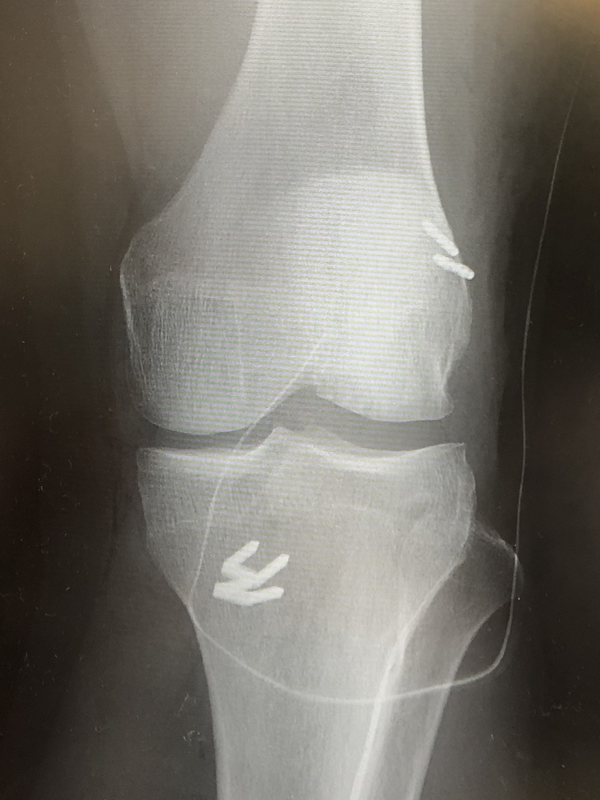

移植腱と骨孔が完成したら、脛骨から大腿骨の骨孔に向けて移植腱を挿入していきます。このとき、移植腱の近位先端にはエンドボタンと呼ばれる金具がついています。また移植腱の遠位は、引っ張ることができるよう強い糸で縛ります。大腿骨の骨孔を通過したあとにエンドボタンを引っくり返すことで、移植腱が骨孔に固定される仕組みです。大腿骨の骨孔にエンドボタンが引っかかったら、移植腱を脛骨骨孔開口部(関節外)から適度の張力をかけて引っ張り、チタン製の固定具で固定します。

当院では、膝下の切開創とは別に、大腿部(太もも)外側を小さく切開して大腿骨の骨孔を作っています。大腿骨側からアプローチし、骨孔の位置決めの自由度を上げるためです。